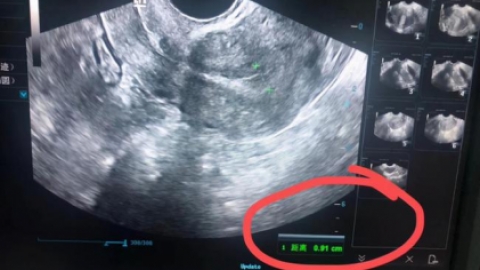

首先观察子宫内膜的厚度,是需要结合月经周期来看,子宫内膜会随月经周期而变化,通常厚度会在1-12mm之间。通常会根据子宫的内膜的变化,将月经周期分为增殖期、分泌期和月经期三个阶段。以一个正常月经周期28日为例,月经的5-14天是增殖期,这个阶段也就是女性月经刚刚结束一直到排卵期左右,这时候的子宫内膜厚度,会从0.5mm...

子宫内膜多少算薄,子宫内膜薄了能怀孕吗?子宫内膜的厚薄呢,在整个月经周期中,他是一个波动性的变化,一般是在经期内膜的厚度,多半是一到四毫米,早卵泡期内膜的厚度是四到八毫米中,晚卵泡期的时候可以达到八到14毫米,排卵以后黄体期的时候,内膜的厚度,可能也

我们经常会提到这个话题,很多准备生育的准宝爸宝妈们努力很久无法怀上宝宝,然后去医院检查却被告知子宫内膜薄,但却不知道怎么回事,那么到底子宫内膜薄是怎么回事呢?子宫内膜为什么会薄呢?咱们先来看看子宫内膜的结构。子宫内膜多薄才算薄呢?正常子宫内膜厚度在月经期约为1~咱们看子宫内膜厚度的一起要看卵泡的巨细。子宫内膜薄是否会影...